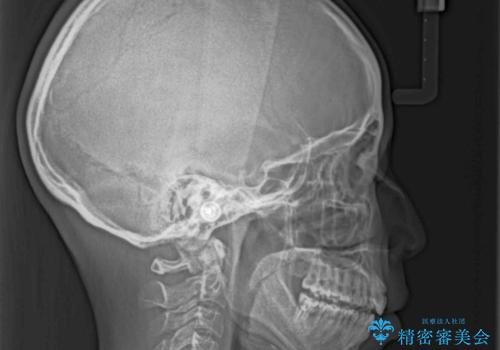

目立たない装置で横顔のシルエットを改善 ハーフリンガルでの抜歯矯正

- 口元の突出感を気にして来院された患者様です。

上下左右の第一小臼歯4本を抜歯して口元を下げる治療計画としました。